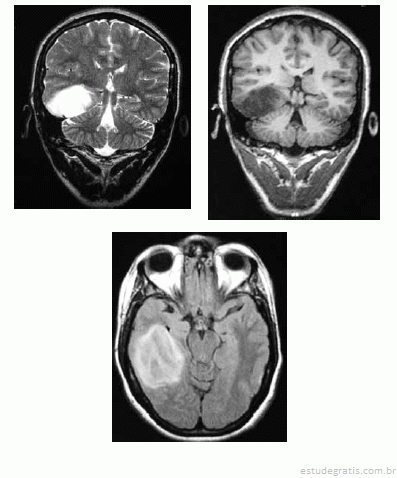

Uma mulher de 36 anos de idade foi encaminhada ao ambulatório de neurologia por dificuldade no controle das crises epilépticas. Ela referiu ter tido uma convulsão febril aos 36 meses e ter passado a ter crises em que ficava “fora do ar” aos 11 anos. Ela recebeu o diagnóstico de epilepsia generalizada do tipo ausência e foi-lhe prescrito fenobarbital. Desde então, já fez uso de primidona, ácido valpróico e diazepam, em monoterapia e associados ao fenobarbital, sem sucesso. No exame, a paciente apresentava um comprometimento da memória recente e aparentava ter um sutil deficit dos campos visuais e Babinski à esquerda. Apesar de trazer um EEG normal, foi solicitada RNM de encéfalo, que é reproduzida abaixo.

A lesão demonstrada na RNM pode significar uma neoplasia infiltrativa de baixo grau de malignidade.Comentários